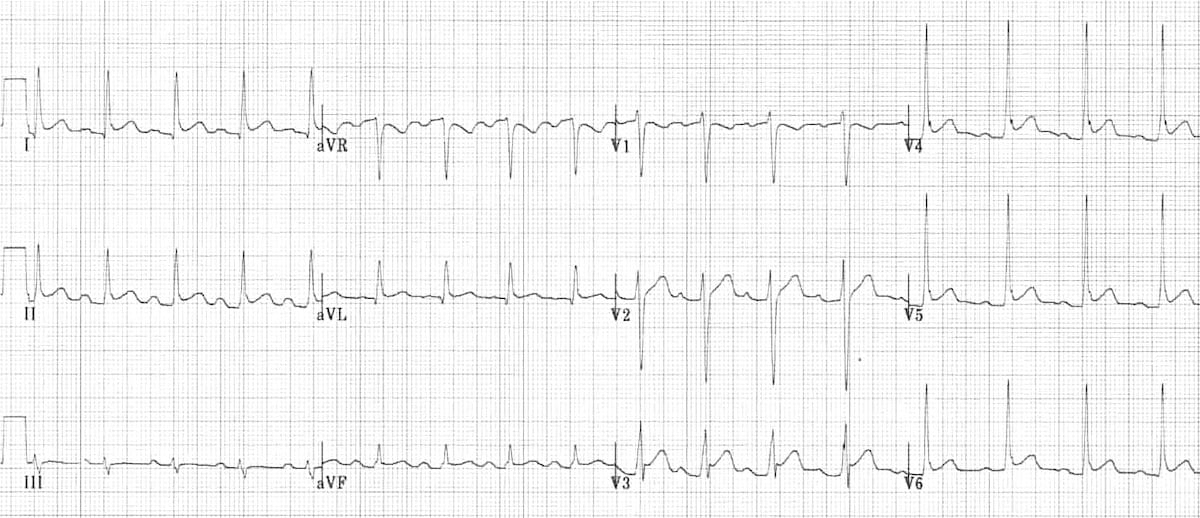

This is an ECG of LBBB. First, note the widened QRS complex across all leads. Second, a deep S wave is seen in V1 along with a dominant R wave in V6. Third, discordant changes are best seen in V1, where there is ST elevation and upright T wave while the QRS is -ve (dominant S wave).

© Life in the Fast Lane. Licensed under CC BY-NC 4.0

This is an EGG of RBBB. First, note the widened QRS complex across all leads. Second, an M-shaped +ve QRS in V1 along with a wide slurred S wave in V6. Third, discordant changes are best seen in V1, where there is T wave inversion while the QRS is +ve (dominant R wave).

© Life in the Fast Lane. Licensed under CC BY-NC 4.0